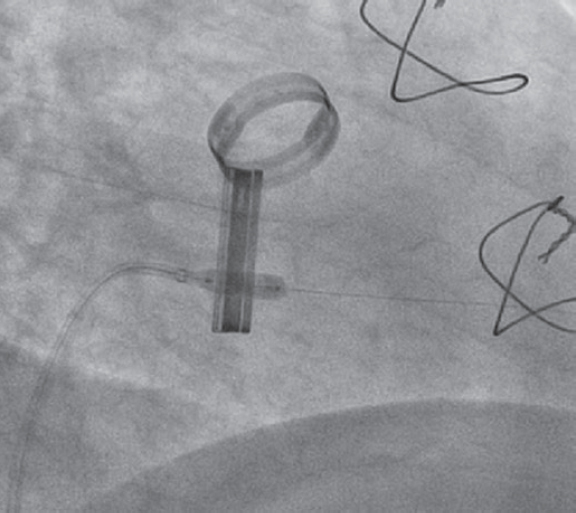

Debido a que el disco estaba bloqueado en una posición casi completamente cerrada (vídeo 1 del material adicional), optamos por un enfoque menos agresivo que el descrito por Jabbour et al.1 y en vez de manipular el disco con el catéter guía decidimos utilizar un catéter balón. Para ello, por el catéter guía se avanzó una guía de 0,014 pulgadas Balance Middleweight hacia las cavidades izquierdas. Aunque el alambre guía tendió a avanzar hacia al ventrículo izquierdo a través del espacio que dejaba el disco móvil al abrirse, después de varios intentos se pudo dirigir a través del pequeño espacio entre el disco bloqueado y el anillo protésico (figura 1) (vídeo 2 del material adicional). Con el extremo de la guía apoyado en el ápex, se avanzó suavemente un catéter balón no distensible Medtronic NC Euphora 5,0 × 15 mm que se infló varias veces a nivel del anillo mitral hasta que el disco bloqueado se liberó por completo (figura 2) (vídeos 3 y 4 del material adicional). La ecocardiografía transesofágica realizada después del procedimiento mostró la normalización de la función de la válvula protésica con un gradiente medio de 5 mmHg y un movimiento adecuado de ambos discos (figura 3). La paciente fue extubada inmediatamente después de la intervención sin complicaciones y no hubo eventos tromboembólicos ni hemorrágicos posteriores. Fue dada de alta 2 días después del procedimiento, con anticoagulantes orales y ácido acetilsalicílico. Un estudio sistemático descartó alteraciones de la coagulación y la paciente permanecía asintomática a los 12 meses de seguimiento.

Figura 2. Catéter balón hinchado a nivel del anillo mitral.